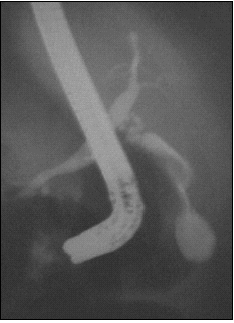

Cet examen se déroule dans une salle équipée d'un matériel de radiologie. Le cathétérisme diagnostique consiste à introduire dans la papille à partir du duodénum un cathéter pour injecter les voies biliaires et/ou pancréatiques avec du produit de contraste. Il est alors réalisé des radiographies.

Radiographie objectivant les voies biliaires opacifiées

et le duodénoscope en forme de J